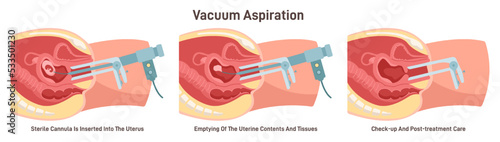

Aspiration - Posters, Wall Art, Canvas Prints